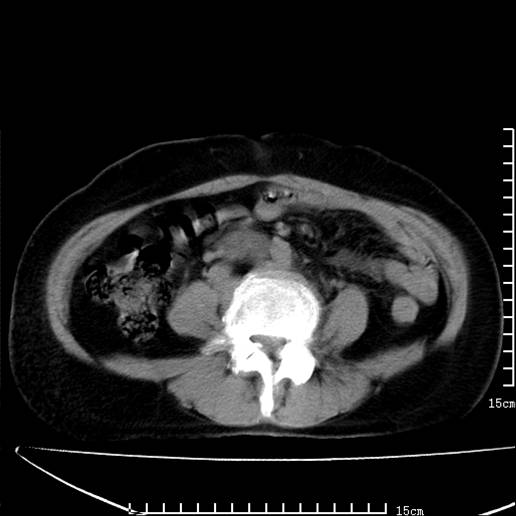

以下是引用pujunzhi在2008-5-30 15:31:00的发言:[br]异位肾—盆腔肾。当看到肾窝无肾脏时,要想到孤立肾和异位肾,异位肾最常见是盆腔肾,偶见胸腔,易误认为肺占位,只要想到就不会漏诊。建议增强扫描。